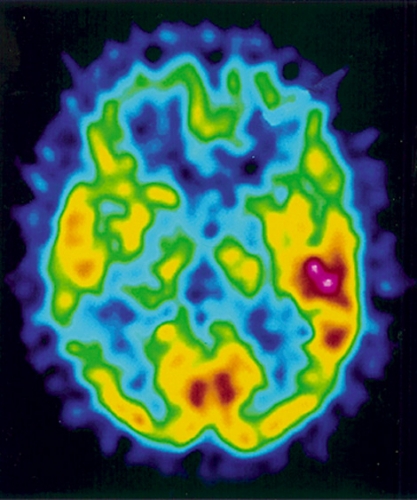

De övriga tillstånden kännetecknas av varierande grad av självmedvetenhet sammanhängande med olika patofysiologisk bakgrund (Figur 1). Minimalt responsivt tillstånd antas återspegla en lägre grad av dekortikering än vegetativa tillstånd, medan akinetisk mutism och paramediant diencefalt syndrom kan orsakas av skador på frontala neuronala nätverk respektive delar av talamus [4].

Prognosen för de olika grupperna är skiftande samtidigt som det finns ökande evidens för effekterna av olika specifika behandlingsstrategier, inklusive farmakologiska. Några av tillstånden kan dessutom avlösa varandra i tiden, vilket är av betydelse i relation till prognosbedömning och planering av behandling (Figur 2). För samtliga grupper gäller att risken för medicinska komplikationer är hög, omvårdnadsbehovet stort och att anhörigkretsen är hårt drabbad. Det finns således behov av kvalificerad både medicinsk, psykosocial och etisk kompetens under det tidiga omhändertagandet [5, 6].